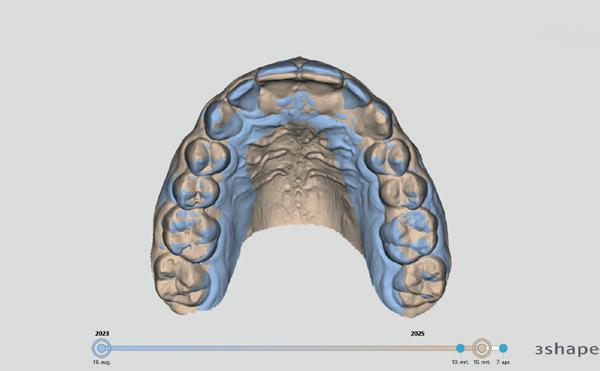

Tijdens het uitvoeren van het onderzoek leek alsof elementen 11 en 21 geen mobiliteit vertoonden en tegelijkertijd was het duidelijk dat ze niet in de juiste positie stonden. In een dergelijk geval, waarbij enige druk nodig is om te reponeren, is het fijn om te weten waar de elementen horen te staan. Het niet in de juiste positie brengen kan zorgen voor een (blijvend) suboptimaal resultaat of een extra lang behandeltraject. Op het moment dat ik bezig was met de vraag ‘Waar horen ze te staan?’, zag ik onze intra-oraal scanner staan en toeval wilde dat er al snel een scan uit 2023 aanwezig was. Deze was gemaakt net na het

afronden van orthodontische behandeling en derhalve een ideale vergelijking. Door een tweetal scans te vervaardigen en deze te matchen, wat ongeveer 3 minuten in totaal kost, kon ik in kaart brengen wat de afwijking was (afbeelding 6-7).